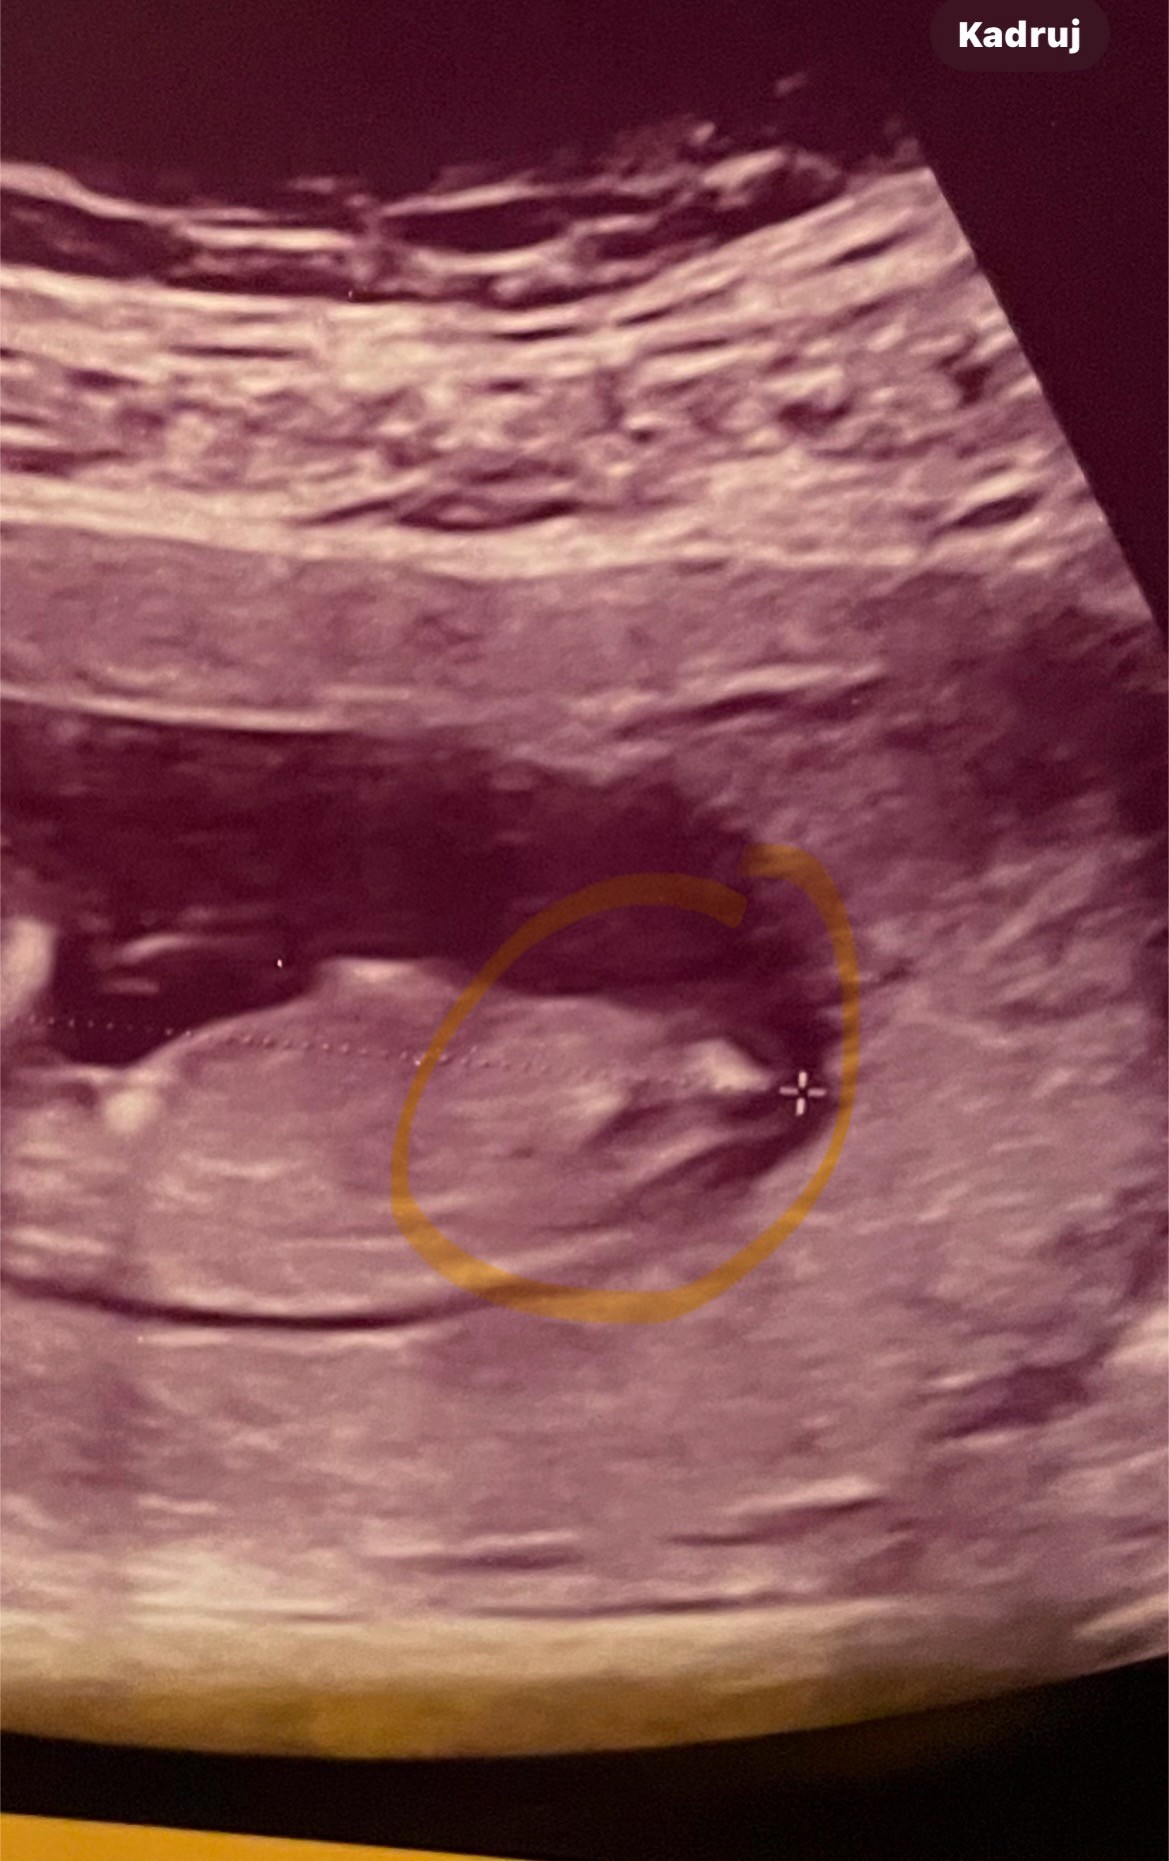

Według was jaka płeć na USG ? 12 tydzieńZobacz załącznik 1674723

To zdjęcie jest strasznie słabej jakości, niemniej jednak skłaniałabym się bardziej ku chłopcu.

To raczej brzmi na zgadywankę a nie stwierdzenie prawdopodobieństwa płci przez lekarza :) Na tym etapie to jest obarczone sporym błędem. Jak chcesz to dla zabawy możesz wstawić zdjęcie usg na grupie na FB „Nub theory”. Jest kilka takich grup i tam się bawią w zgadywanie z nuba :D Twoje zdjęcie jest dosyć specyficzne, dziwnie widoczny jest nub, ja nie jestem pewna, chociaż dałabym tak 60 do 40 na dziewczynkę.